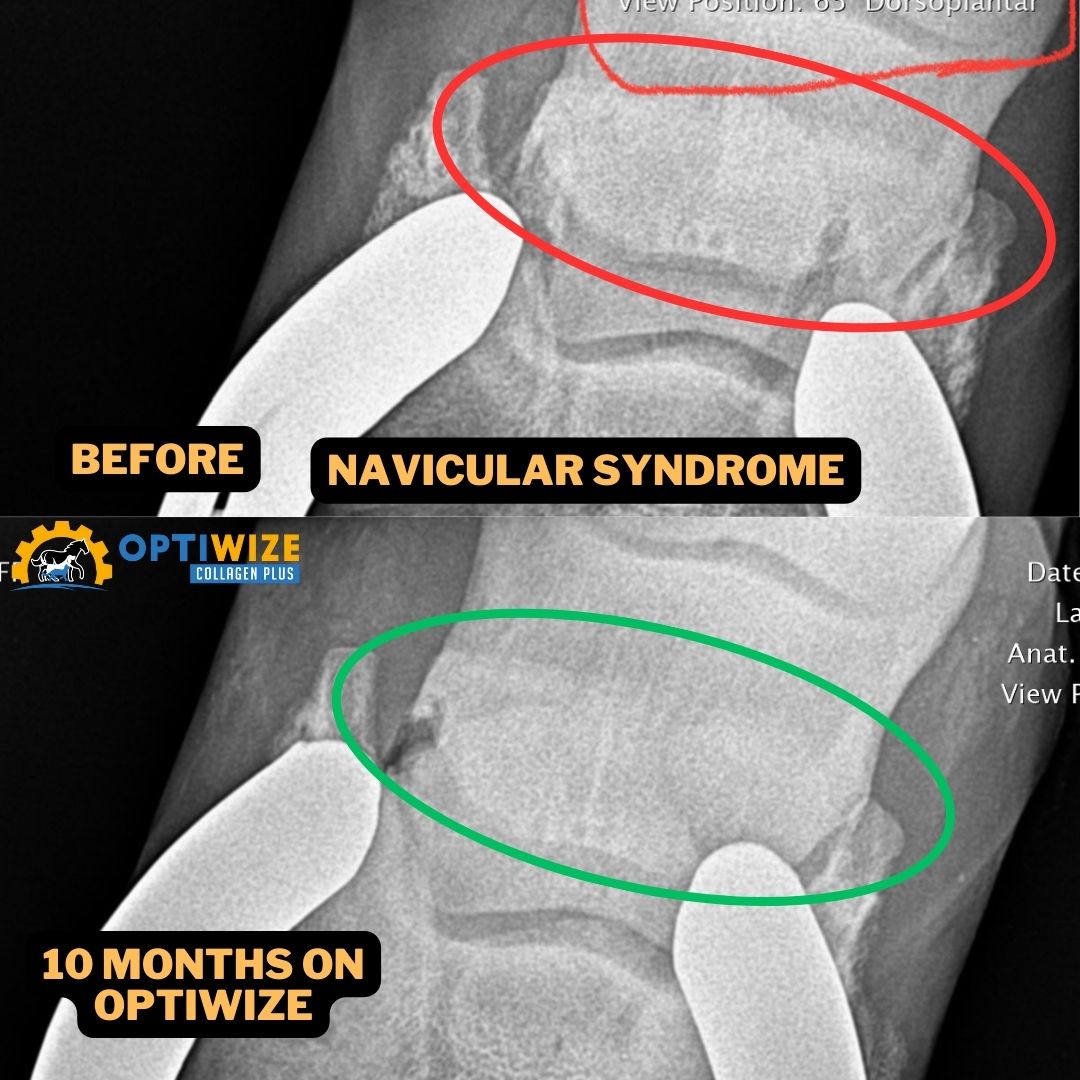

• Equine Navicular, horse navicular supplement, horse collagen supplement, navicular rehab supplement, navicular rehab, severe navicular case